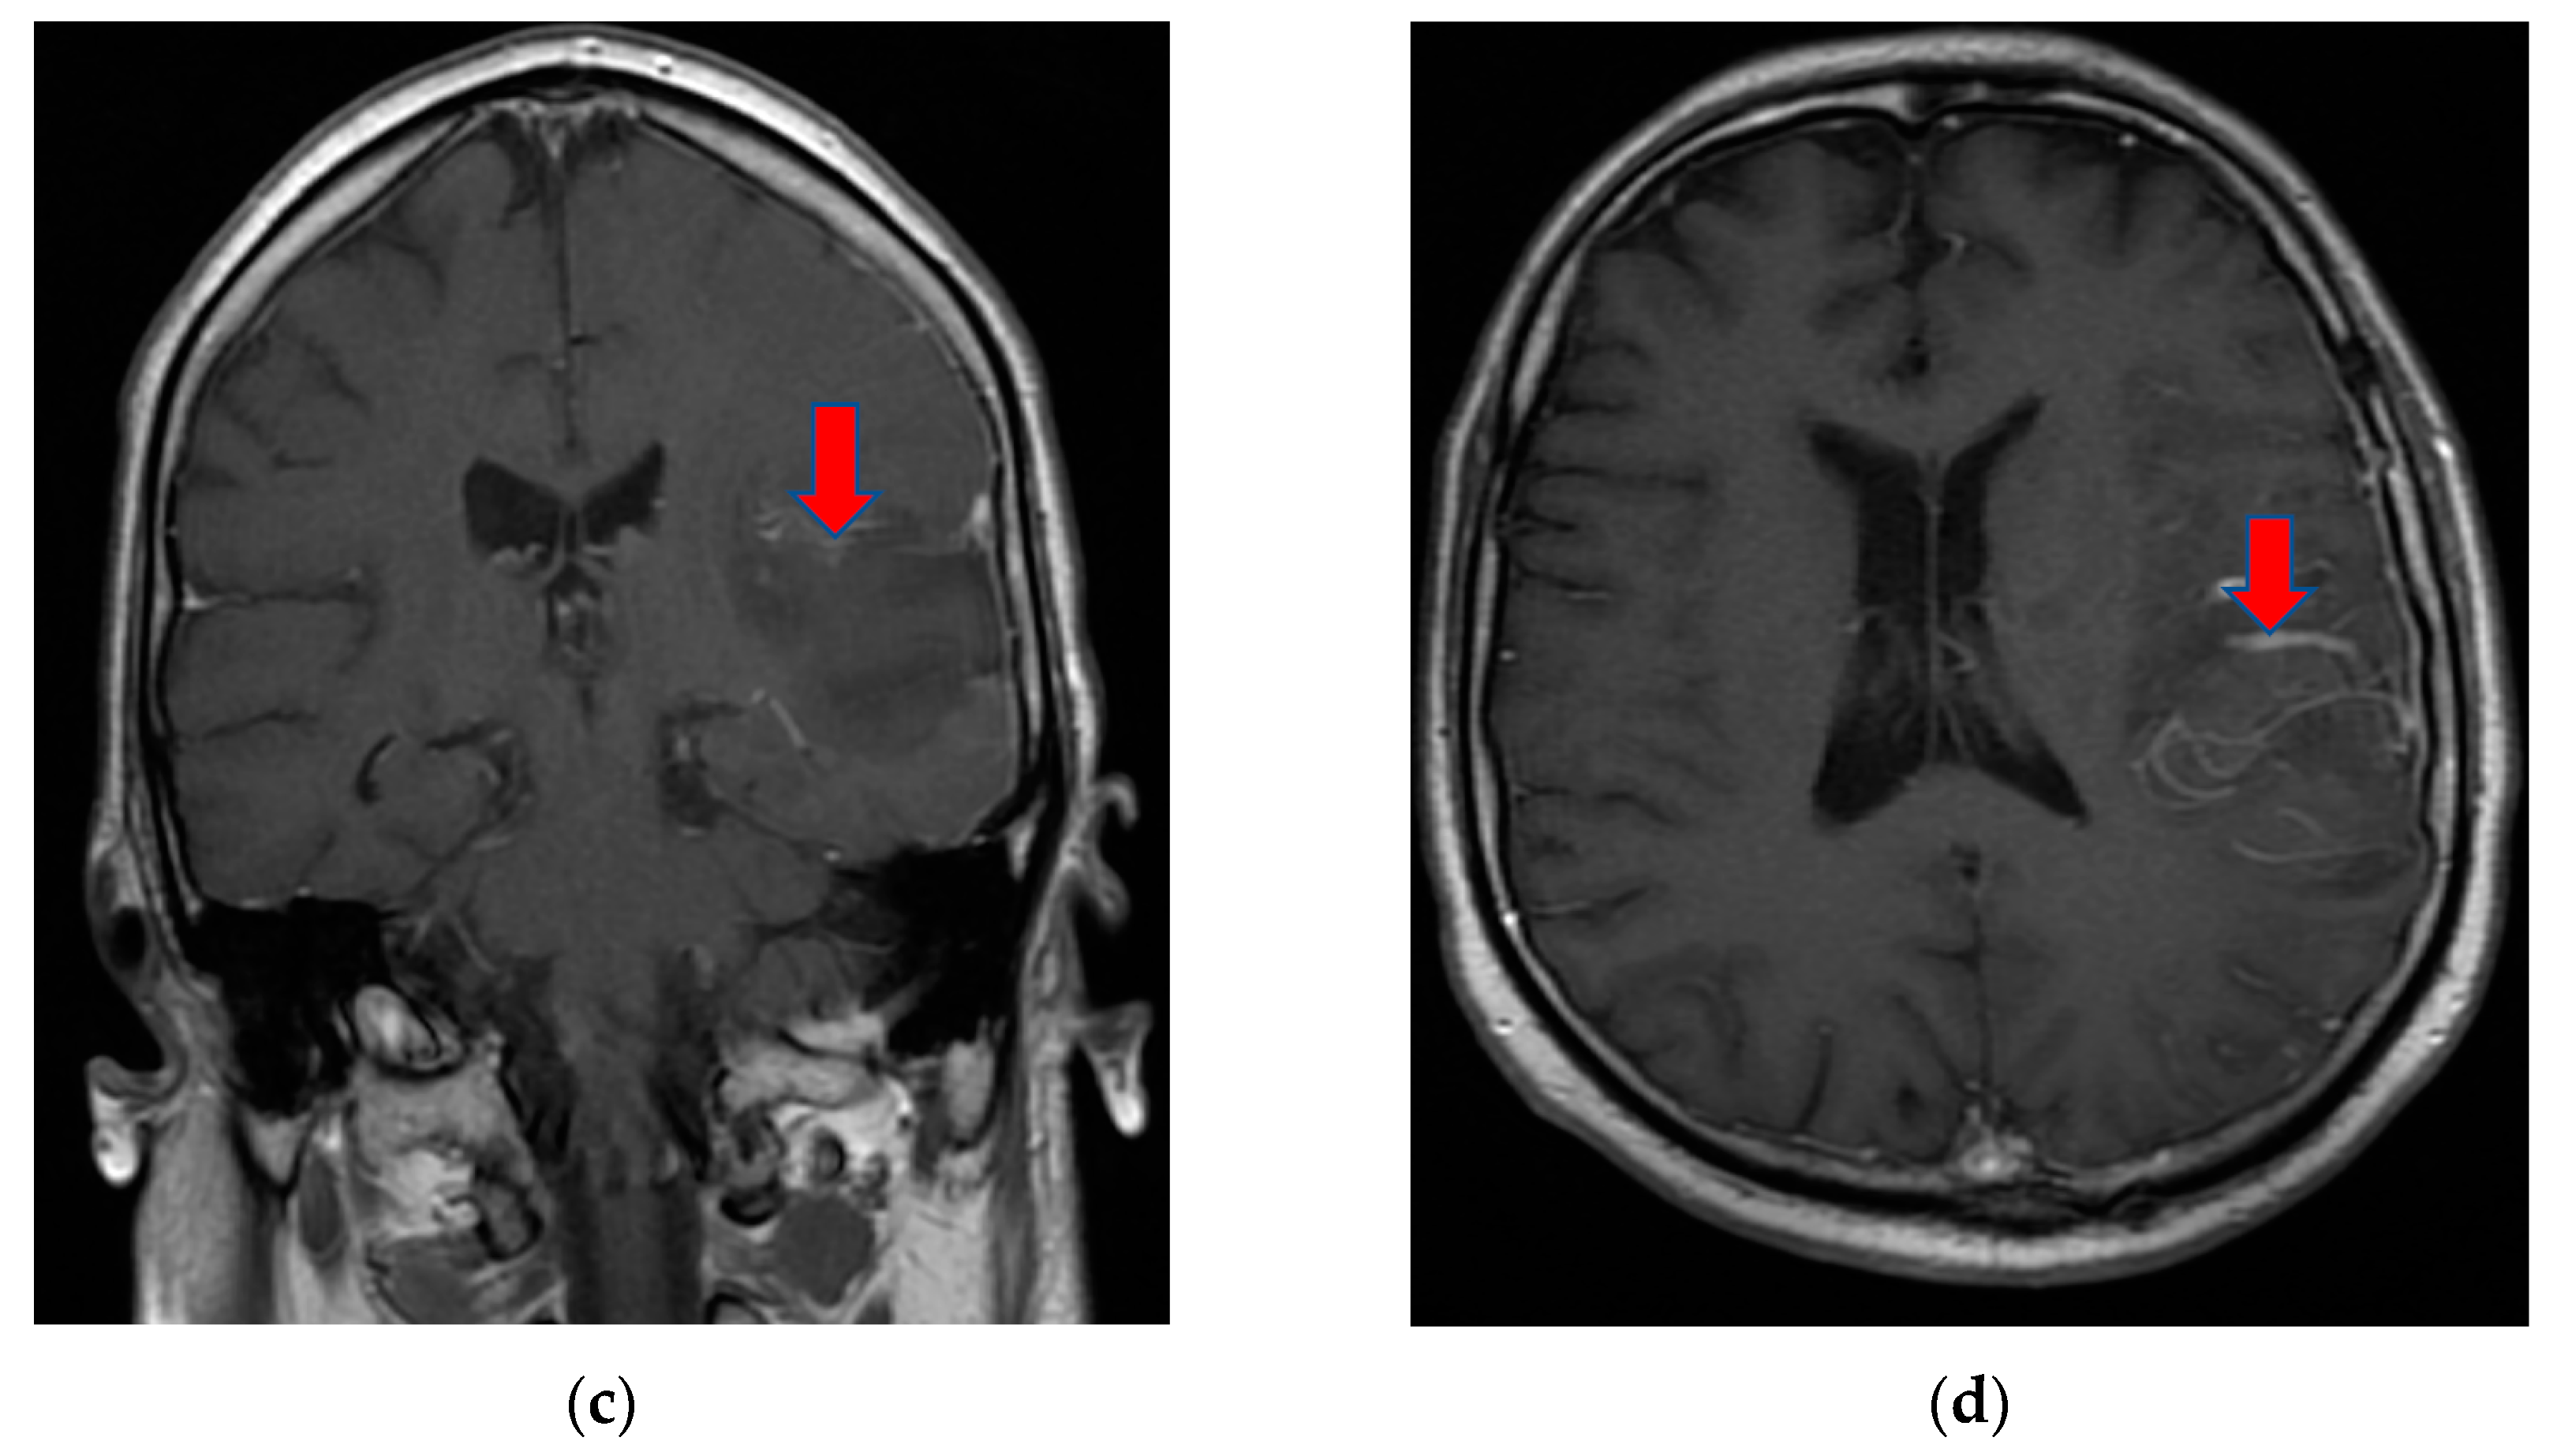

The patient returned after one month to the emergency department with right hemiparesis, mixed aphasia, incomplete left ophthalmoplegia, severe headache, and agitation, without fever. He was tested again for SARS-CoV-2 with nasal polymerase chain reaction (RT-PCR) and was found to be positive. His vitals were stable and non-contrast brain CT showed left capsulo-lenticular and temporal hypodensities. MRI brain images with and without contrast showed aspects in T2, Flair, and DWI hypersignal without contrast capture of the left temporal cortex, respectively, the hippocampal and ipsilateral parahippocampal region. An MRI brain scan also revealed multiple images in hypersignal T2, Flair, and DWI with dimensions of 2–10 mm located juxtacortically and deeply periventricular fronto-temporo-parietal bilateral. The appearance was suggestive of encephalitis (Figure 2).

Figure 2.

MRI brain images with contrast showed aspects of T2 axial Flair hypersignal in the left temporal lobe (a,b), respectively, in the hippocampal and parahippocampal region (c). The lesion is hyperintense on the DWI axial image (d). MRI: magnetic resonance imaging; Flair: fluid attenuated inversion recovery; DWI: diffusion weighted imaging.